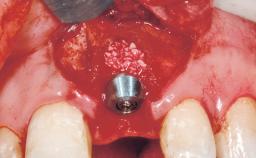

Bone Augmentation Horizontal|Simultaneous

Augmentation Materials Autogenous chips|Membrane

Placement Protocol Immediate implant placement

Socket Integrity Sufficient, with intact bone walls

Bone Volume Sufficient, with intact walls